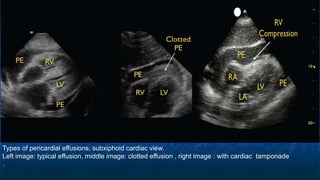

FAST: Subxiphoid exam

Pericardial Effusion

Types of pericardial effusions, subxiphoid cardiac view.

Left image: typical effusion, middle image: clotted effusion , right image : with cardiac tamponade